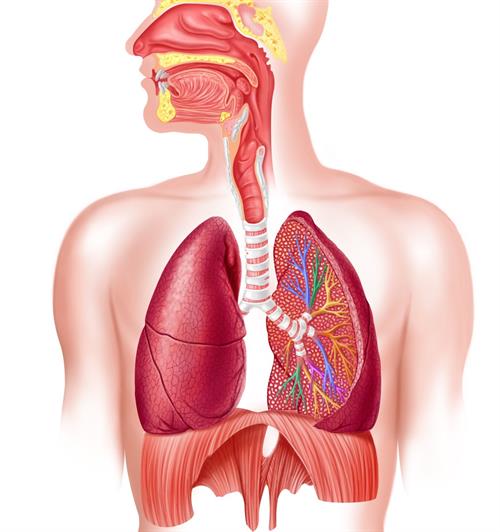

Структурно функциональная единица легких — это основной элемент, который обеспечивает газообмен в организме человека. Именно благодаря этой единице мы получаем кислород и выводим углекислый газ, что критически важно для жизнедеятельности. В этой статье рассмотрим, как именно функционирует эта структура, какие проблемы могут возникать и какие статистические данные подтверждают её значение.

Под этим понятием понимают альвеолярную единицу, или так называемый ацинус — совокупность альвеол, которые получают воздух от одного терминального бронхиола. Это наименьшая единица легкого, которая принимает непосредственное участие в газообмене.

Эти компоненты вместе образуют сложную, но эффективную систему, обеспечивающую жизненно необходимую функцию — дыхание.

Анатомически альвеолярная единица состоит из нескольких структурных элементов, каждый из которых выполняет свою специфическую функцию. Ниже представлена таблица, иллюстрирующая строение и роль основных компонентов.

После вдоха воздух попадает в бронхи, далее — в бронхиолы и, в конечном итоге, доходит до альвеол. Здесь кислород проходит через стенку альвеолы, далее — через стенку капилляра и связывается с гемоглобином эритроцитов. В обратном направлении выводится углекислый газ.